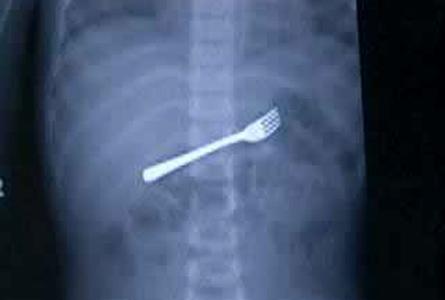

Şoke eden röntgen filmleri

Bu röntgen filmleri görenleri şaşkına çeviriyor!